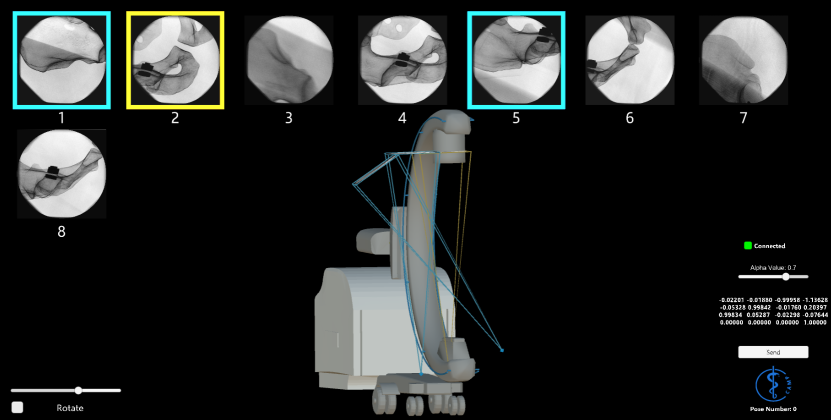

Refer to caption

Figure 3: Multiple flying frustum are rendered at their corresponding 3D pose. The applications running on the computer and the HMD allows the users to replay various acquisition during or after the intervention.

where R={ri,j}i,j:1, 2, 3𝑅subscriptsubscript𝑟𝑖𝑗:𝑖𝑗123R=\left\{r_{i,j}\right\}_{i,j:1,\,2,\,3}. Fig. 3 demonstrates multiple flying frustums, each rendered given their respective 3D pose.